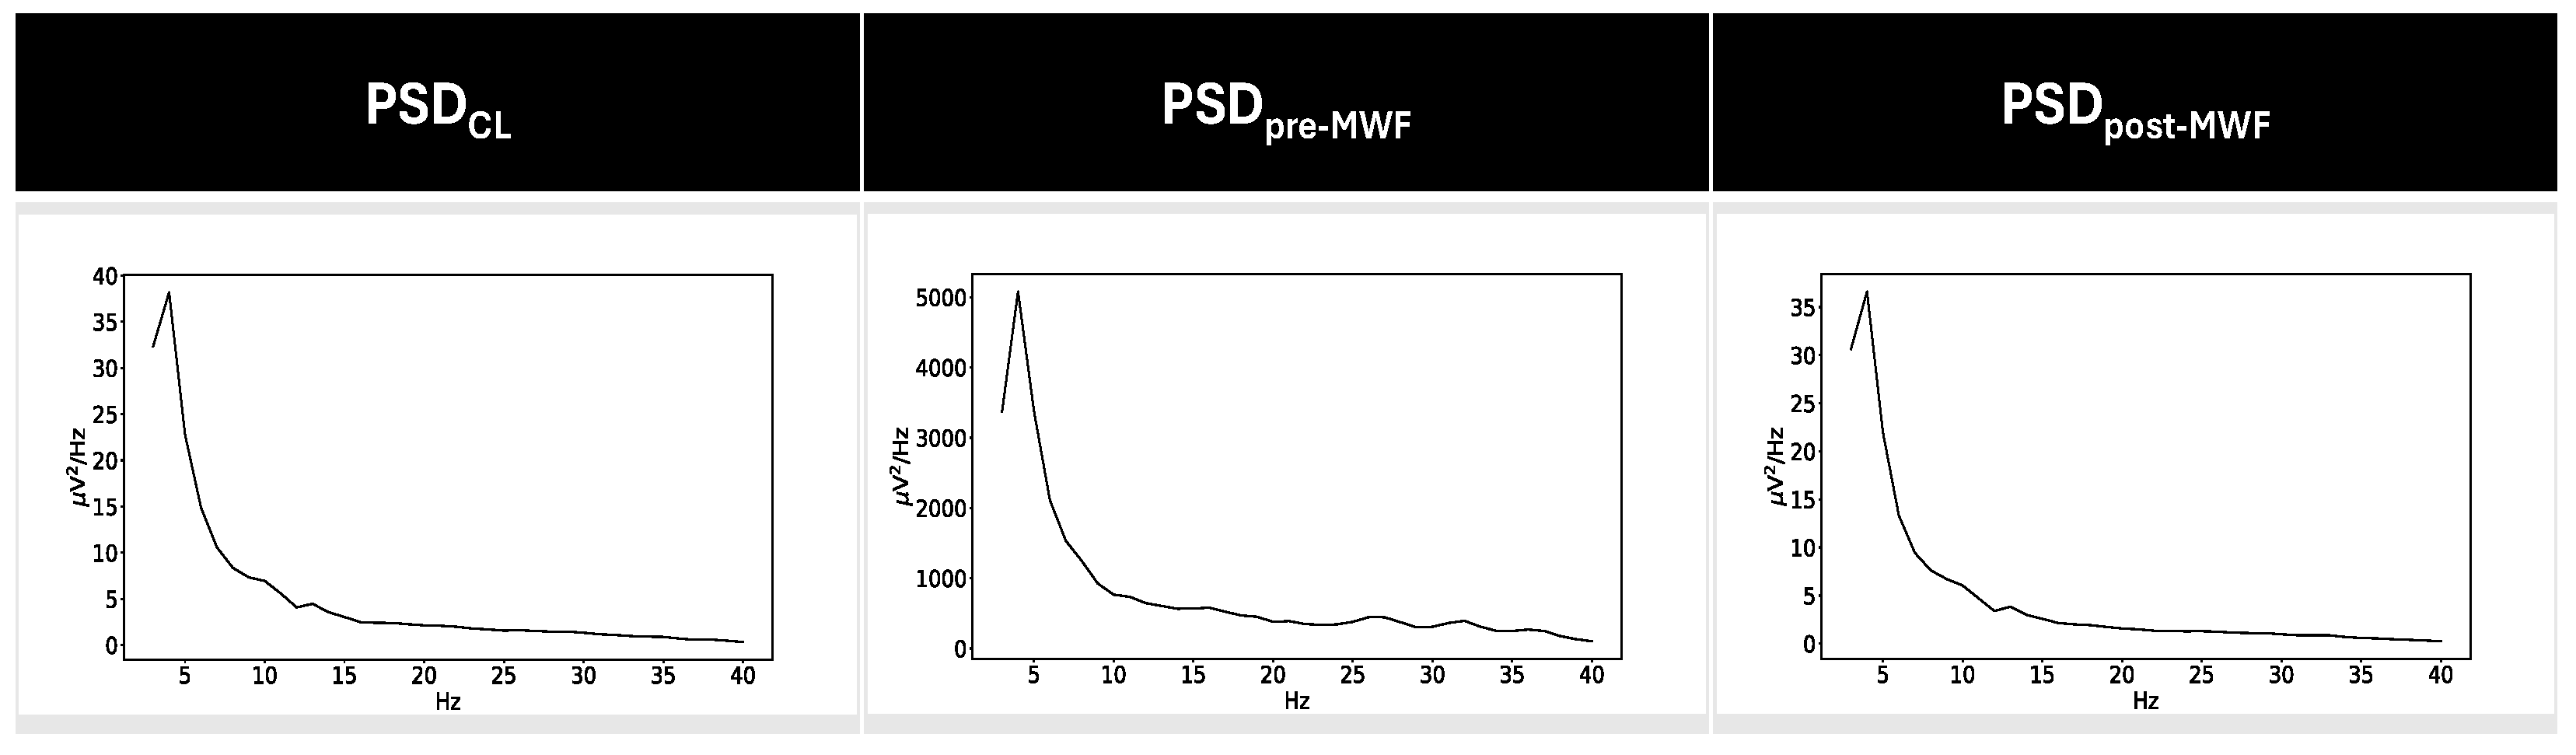

3.1. CI Artifact Characterization

3.2. CI Artifact Reduction